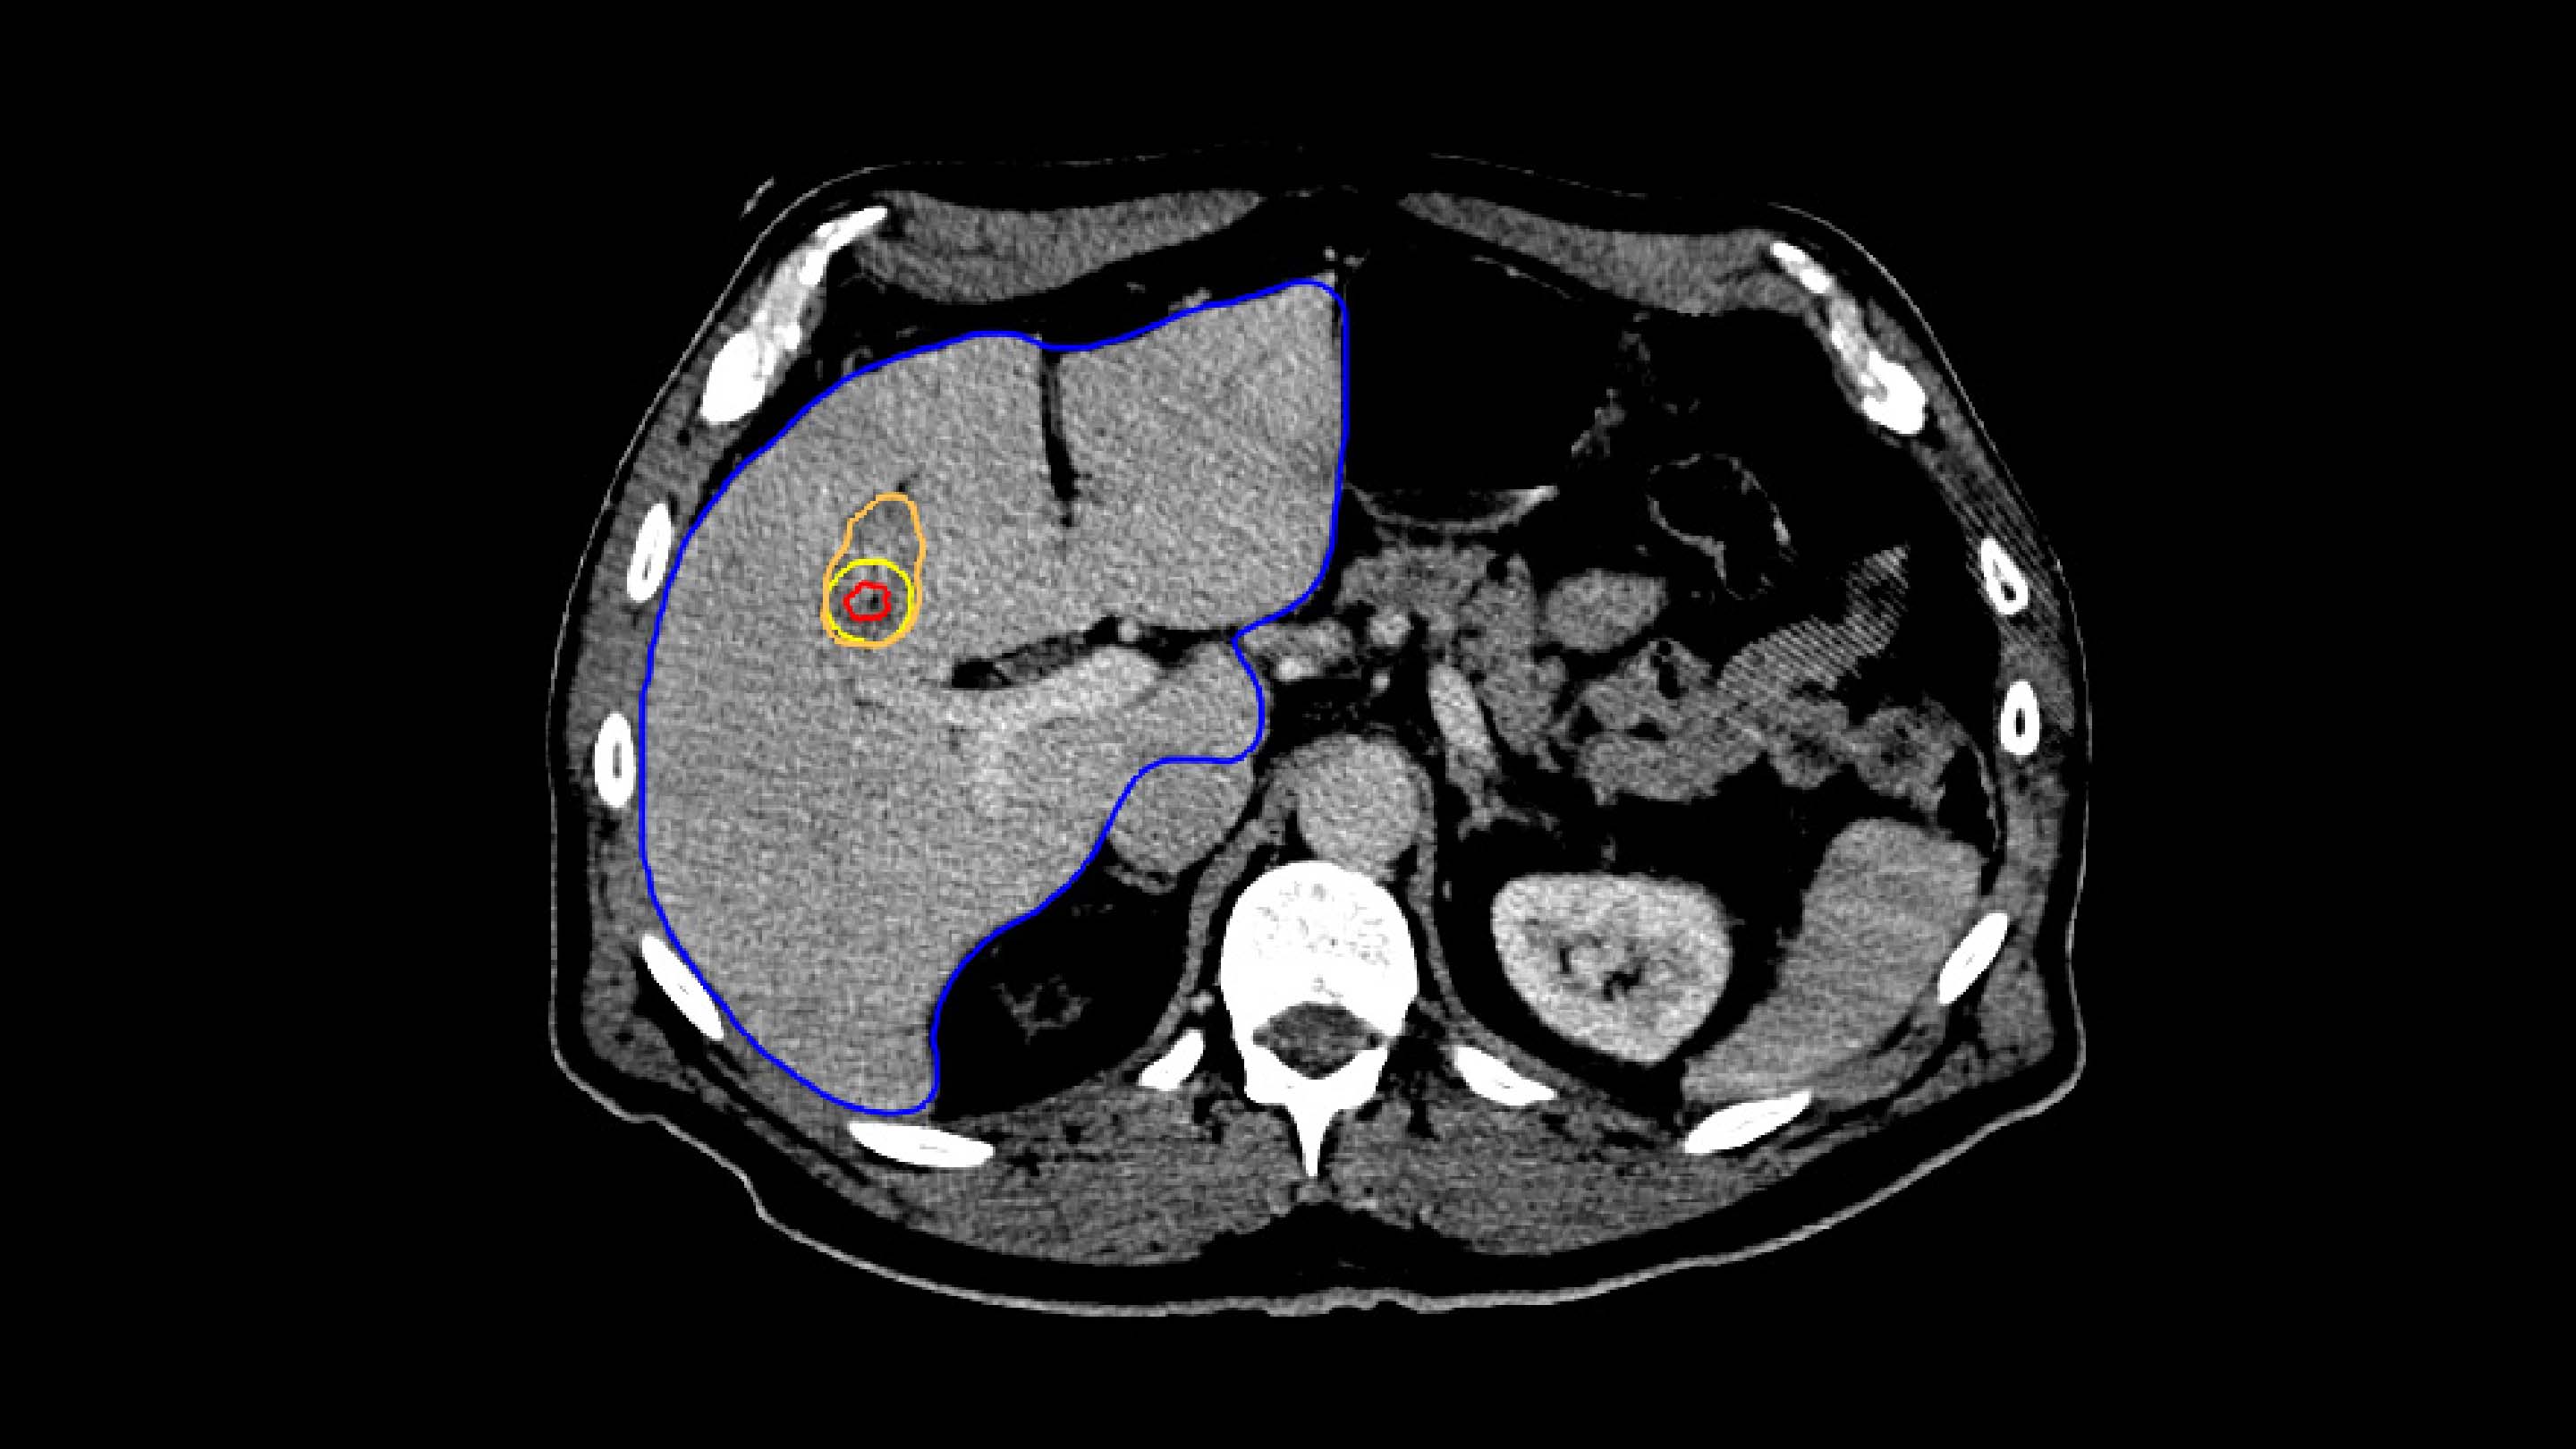

For treatment verification, both the minimal ablative margin calculation and visual inspection based on deformable mapped tumors are provided in the Liver Ablation module.

In Paulucci et al., it was shown that using biomechanical deformable registration, the local disease progression risk decreased to less than 1% with an intraprocedurally confirmed minimum ablative margin greater than 4.6 mm.